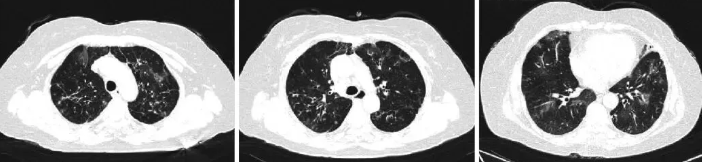

查体:口唇发绀,无杵状指,双肺可闻及湿啰音。心脏无明显异常,双下肢无明显水肿。入院后查血气分析(FiO2:21%):pH 7.47,PaO2 45 mmHg(1 mmHg=0.133 kPa),PaCO2 40 mmHg,SO2 84%。血常规:白细胞计数10.011×109/L,嗜酸性粒细胞计数0.00×109/L,淋巴细胞计数0.97×109/L,淋巴细胞计数百分比9.7%。糖类抗原19-9:38.4 U/nL;糖类抗原72-4:7.75 U/mL;细胞角蛋白19片段:3.39 ng/nL。免疫球蛋白、类风湿因子、高敏肌钙蛋白T、血管紧张素转化酶等检查结果未见明显异常。淋巴细胞亚群绝对计数检测:淋巴细胞百分比5.59 %,B细胞百分比6.3 %,淋巴细胞计数604个/μL,总T细胞计数433个/μL,辅助/诱导细胞计数258个/μL,抑制性/细胞毒细胞计数164个/μL,B细胞计数38个/μL,NK细胞计数129个/μL,NKT细胞计数11个/μL。抗U1-小核糖核蛋白抗体(A-U1-snRNP)弱阳性,抗史密斯D1抗体(SmD1)弱阳性,抗组蛋白抗体(AHA)弱阳性。抗核抗体(ANA)均质型,1∶320。抗磷脂综合征、抗中性粒细胞胞浆抗体组套阴性,总IgE等检查结果未见明显异常。肺功能提示小气道功能障碍(操作过程中频繁咳嗽可能影响检查结果),肺一氧化碳弥散量60%~79.9%预计值,轻度弥散功能障碍。追溯病史,患者2016年曾行PET/CT检查,调取影像CT发现,肺部间质性改变(图3)。考虑胸腺瘤相关自身免疫所致间质性肺病,加用激素40 mg 3天后患者症状明显好转出院。

图3 患者2016年PET/CT肺部影像

前纵隔占位,两肺见斑片状、索条状高密度影,部分周围见囊状、柱状支气管影;纵隔淋巴结稍大;两侧胸膜增厚。